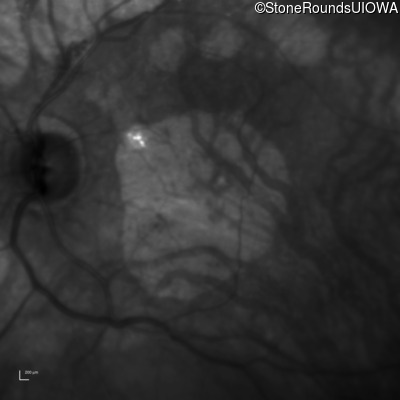

Infrared Fundus Photograph - Left - 20/80

Exemplar